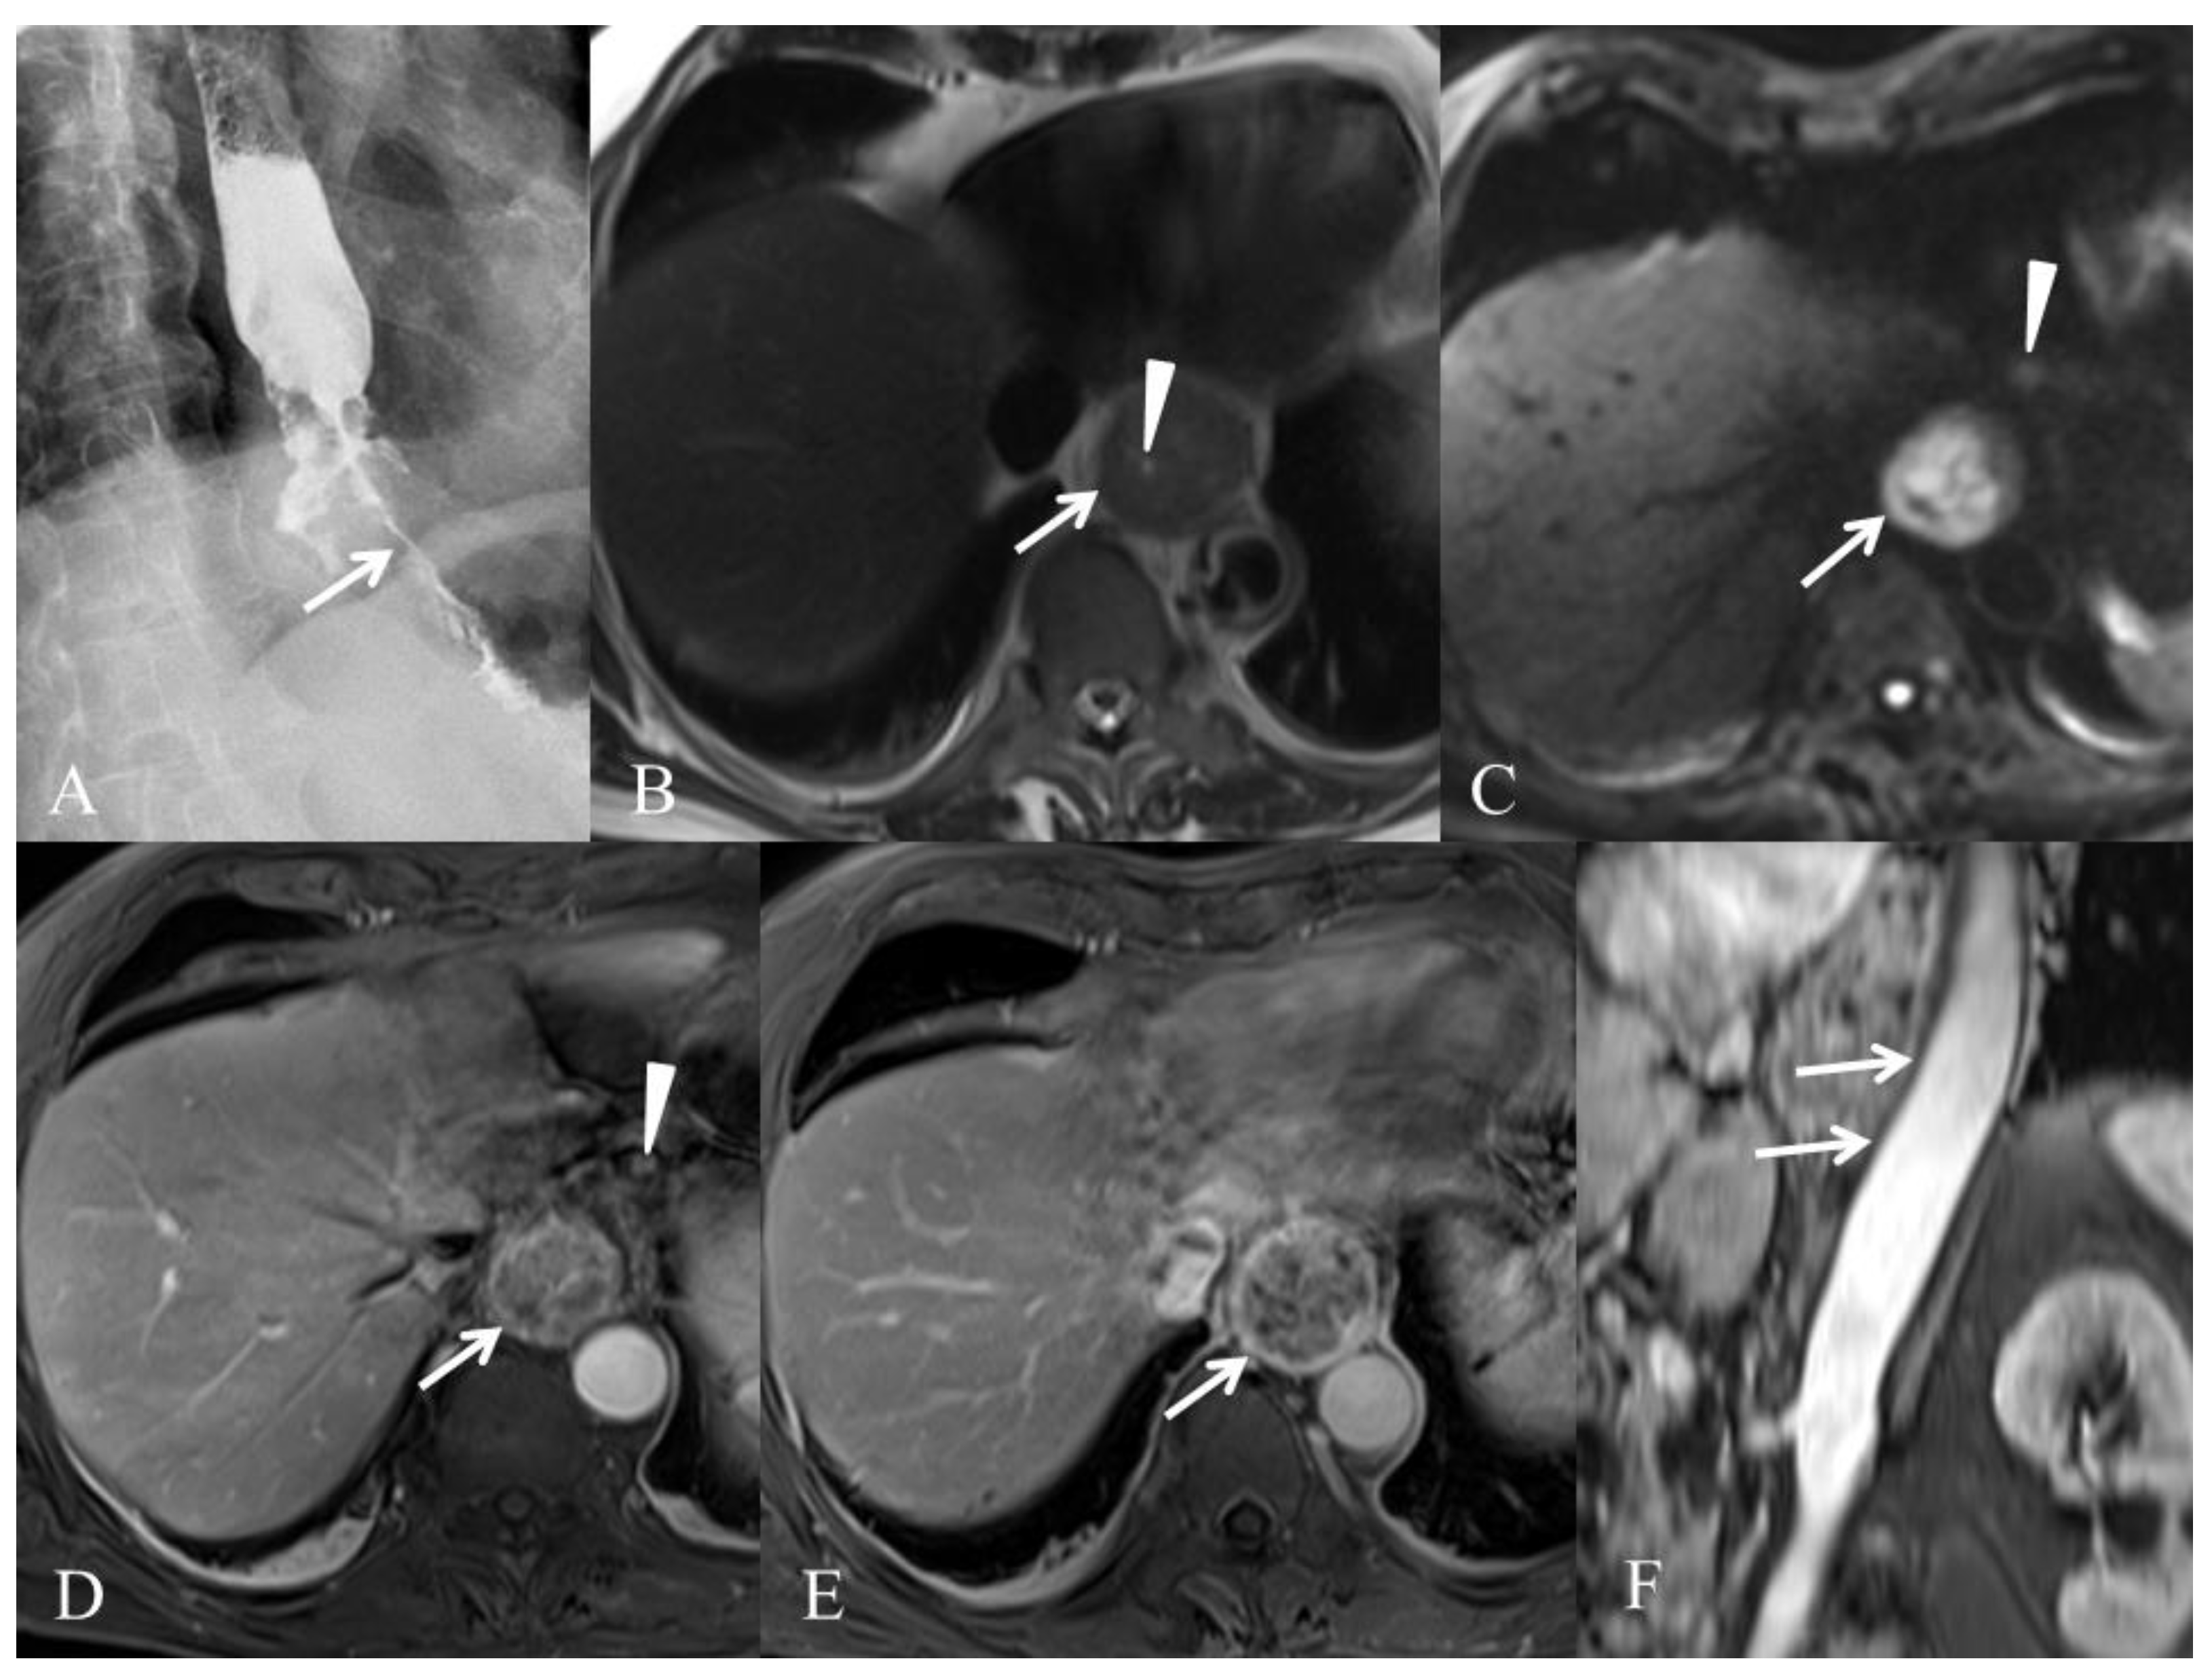

3.3. Metastases (M) Staging